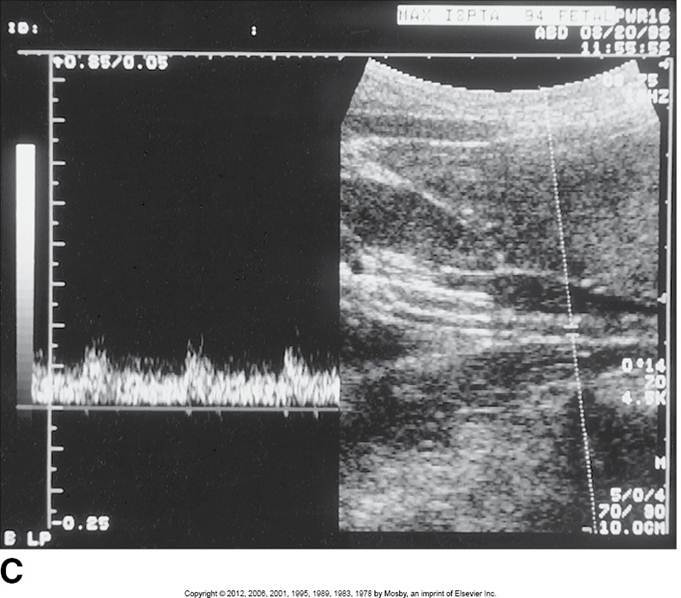

Proximal aorta

High systolic peak

Low diastolic comp.

Clean window